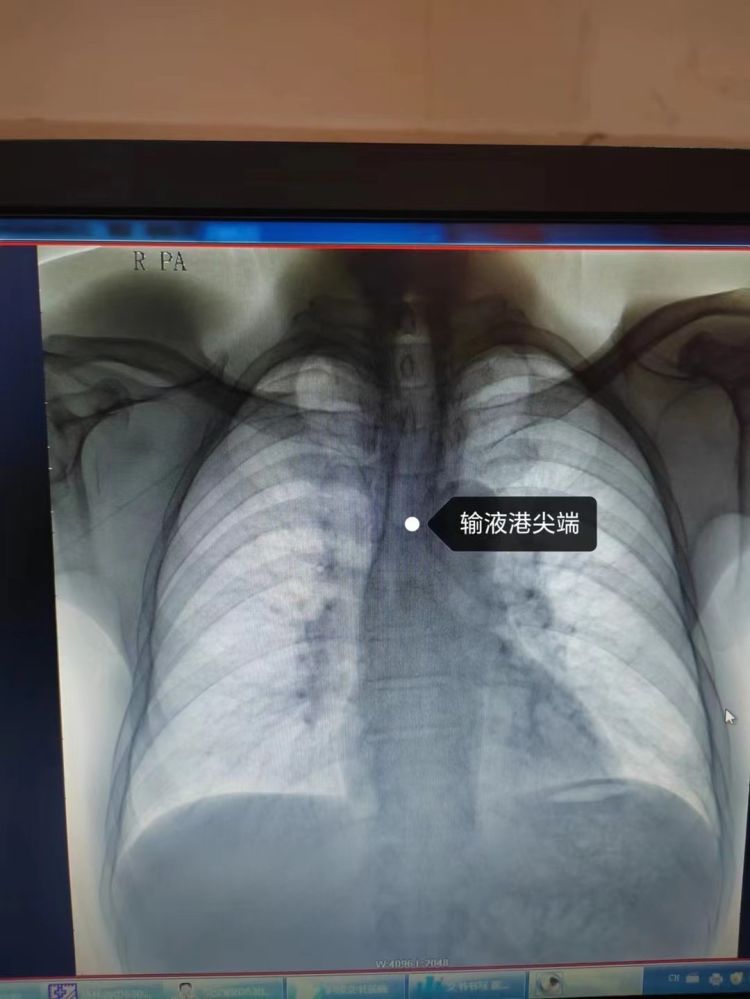

近日,我院肿瘤科成功完成了院内首例输液港植入术,这一创新技术的开展,标志着医院在血管通路技术方面取得了新的突破,更为肿瘤及需长期输液的患者带来了福音,减轻了他们的穿刺痛苦,为他们搭建起一个生命的“港湾”。

输液港,全称为植入式静脉给药装置,是一种完全植入到体内的闭合的静脉输液系统。它通过手术将导管埋入到患者的皮下,形成一条长期、稳定的静脉通道,可以持续为患者提供输液服务。这个“生命港”最长可以在患者体内留置20年以上。

对于需要长期接受高浓度化疗药物、全胃肠外营养、输血以及血样采集等治疗的患者来说,输液港无疑是一个理想的选择。输液港的植入,不仅为患者提供了更加舒适的治疗方式,也极大地减轻了医护人员的工作负担。以往,医护人员需要频繁地为患者进行静脉穿刺,不仅增加了工作量,也给患者带来了不少痛苦。而输液港的植入,使得患者可以在治疗间歇期带管回家,极大地提高了他们的生活质量。